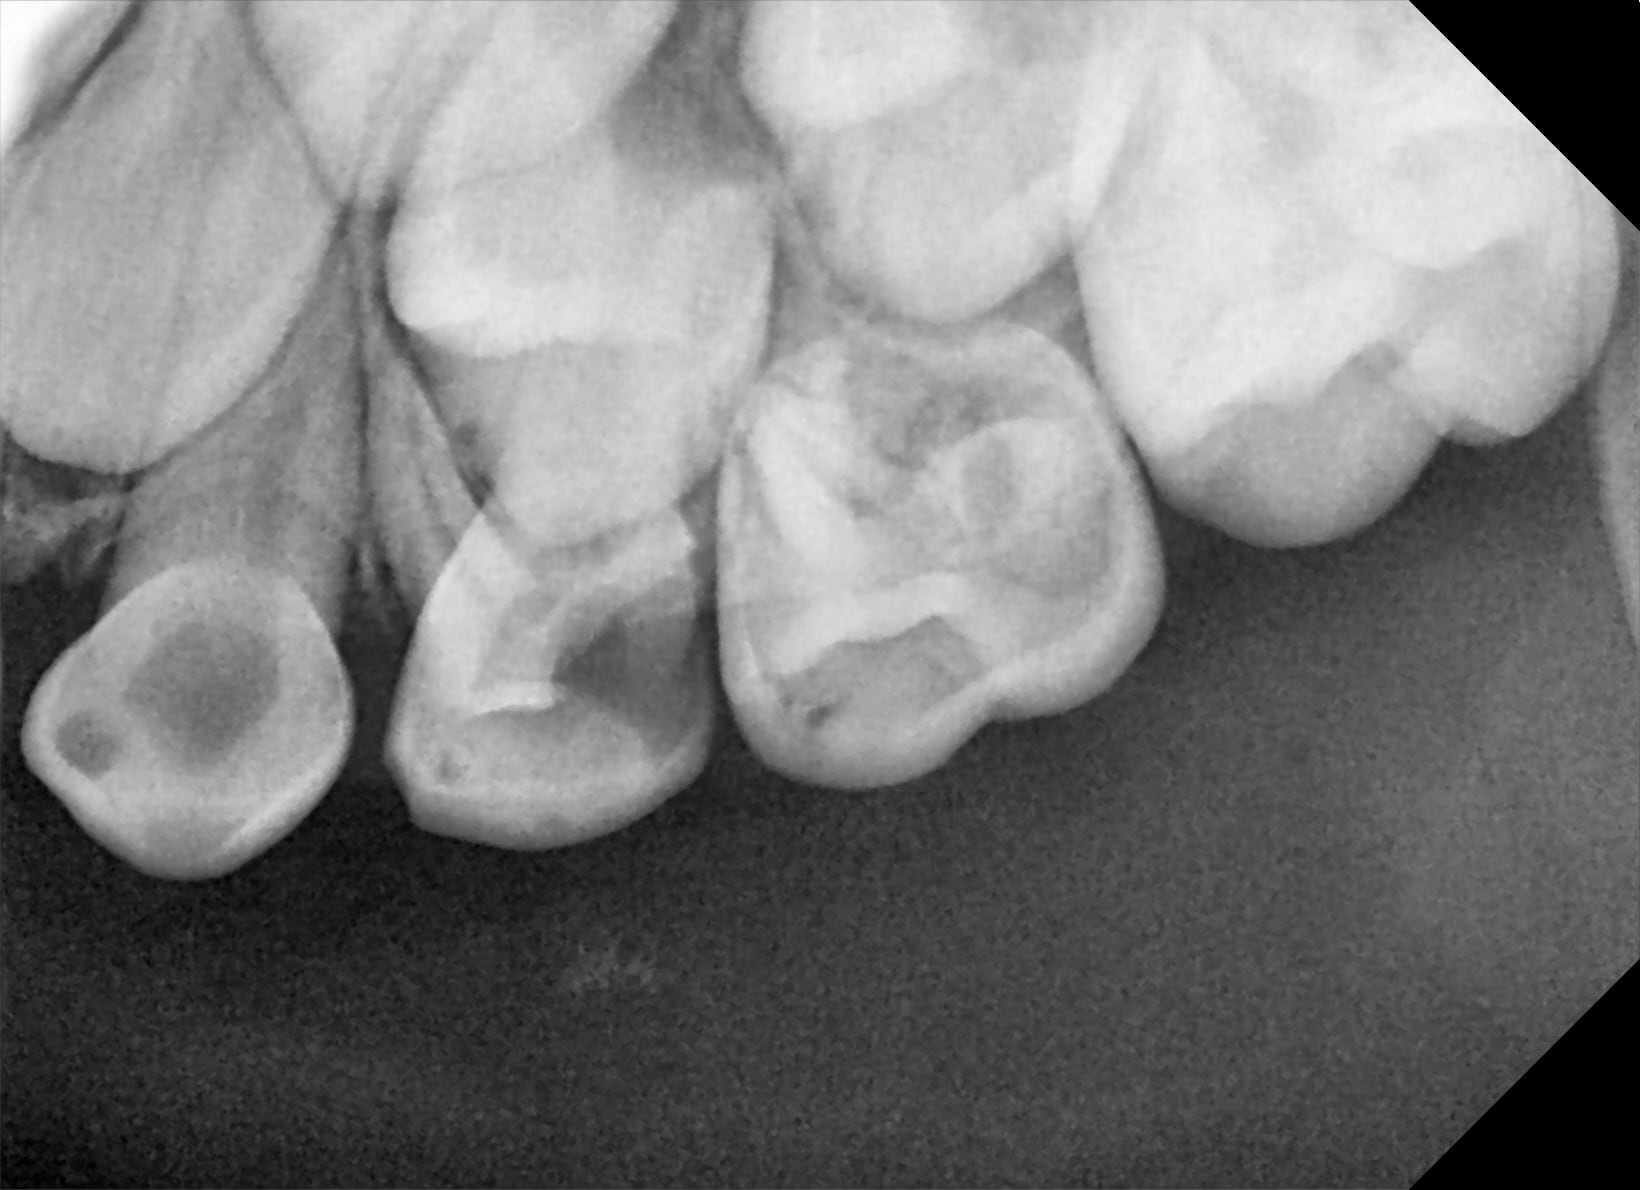

Non_endo_4_2019-09-03_19.24.15_tarfev.png